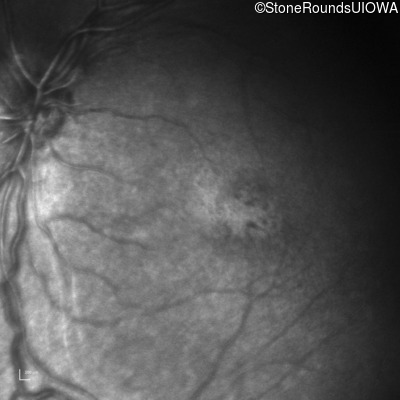

XL Retinoschisis (IIIB1)

Age at visit: 6 years

This 6 year old boy began sitting very close to the television at age 2.

Diagnosis & molecular findings

XL Retinoschisis RS1 Tyr93Stop TAT>TAG   XL